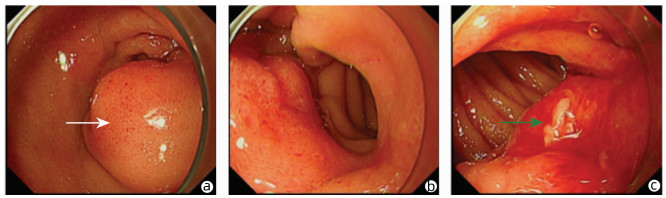

Successful treatment of Bouveret ' s syndrome due to giant duodenal gallbladder stones through the anterior wall of the stomach: A case report

Xu CHEN, Lunxu LI, Bing QI, Qingkai ZHANG, Guixin ZHANG, Shuang LI, Dong SHANG

2022, 38(3): 636-638. DOI: 10.3969/j.issn.1001-5256.2022.03.028

Abstract(896) HTML (227) PDF (2628KB)(43)

Abstract: